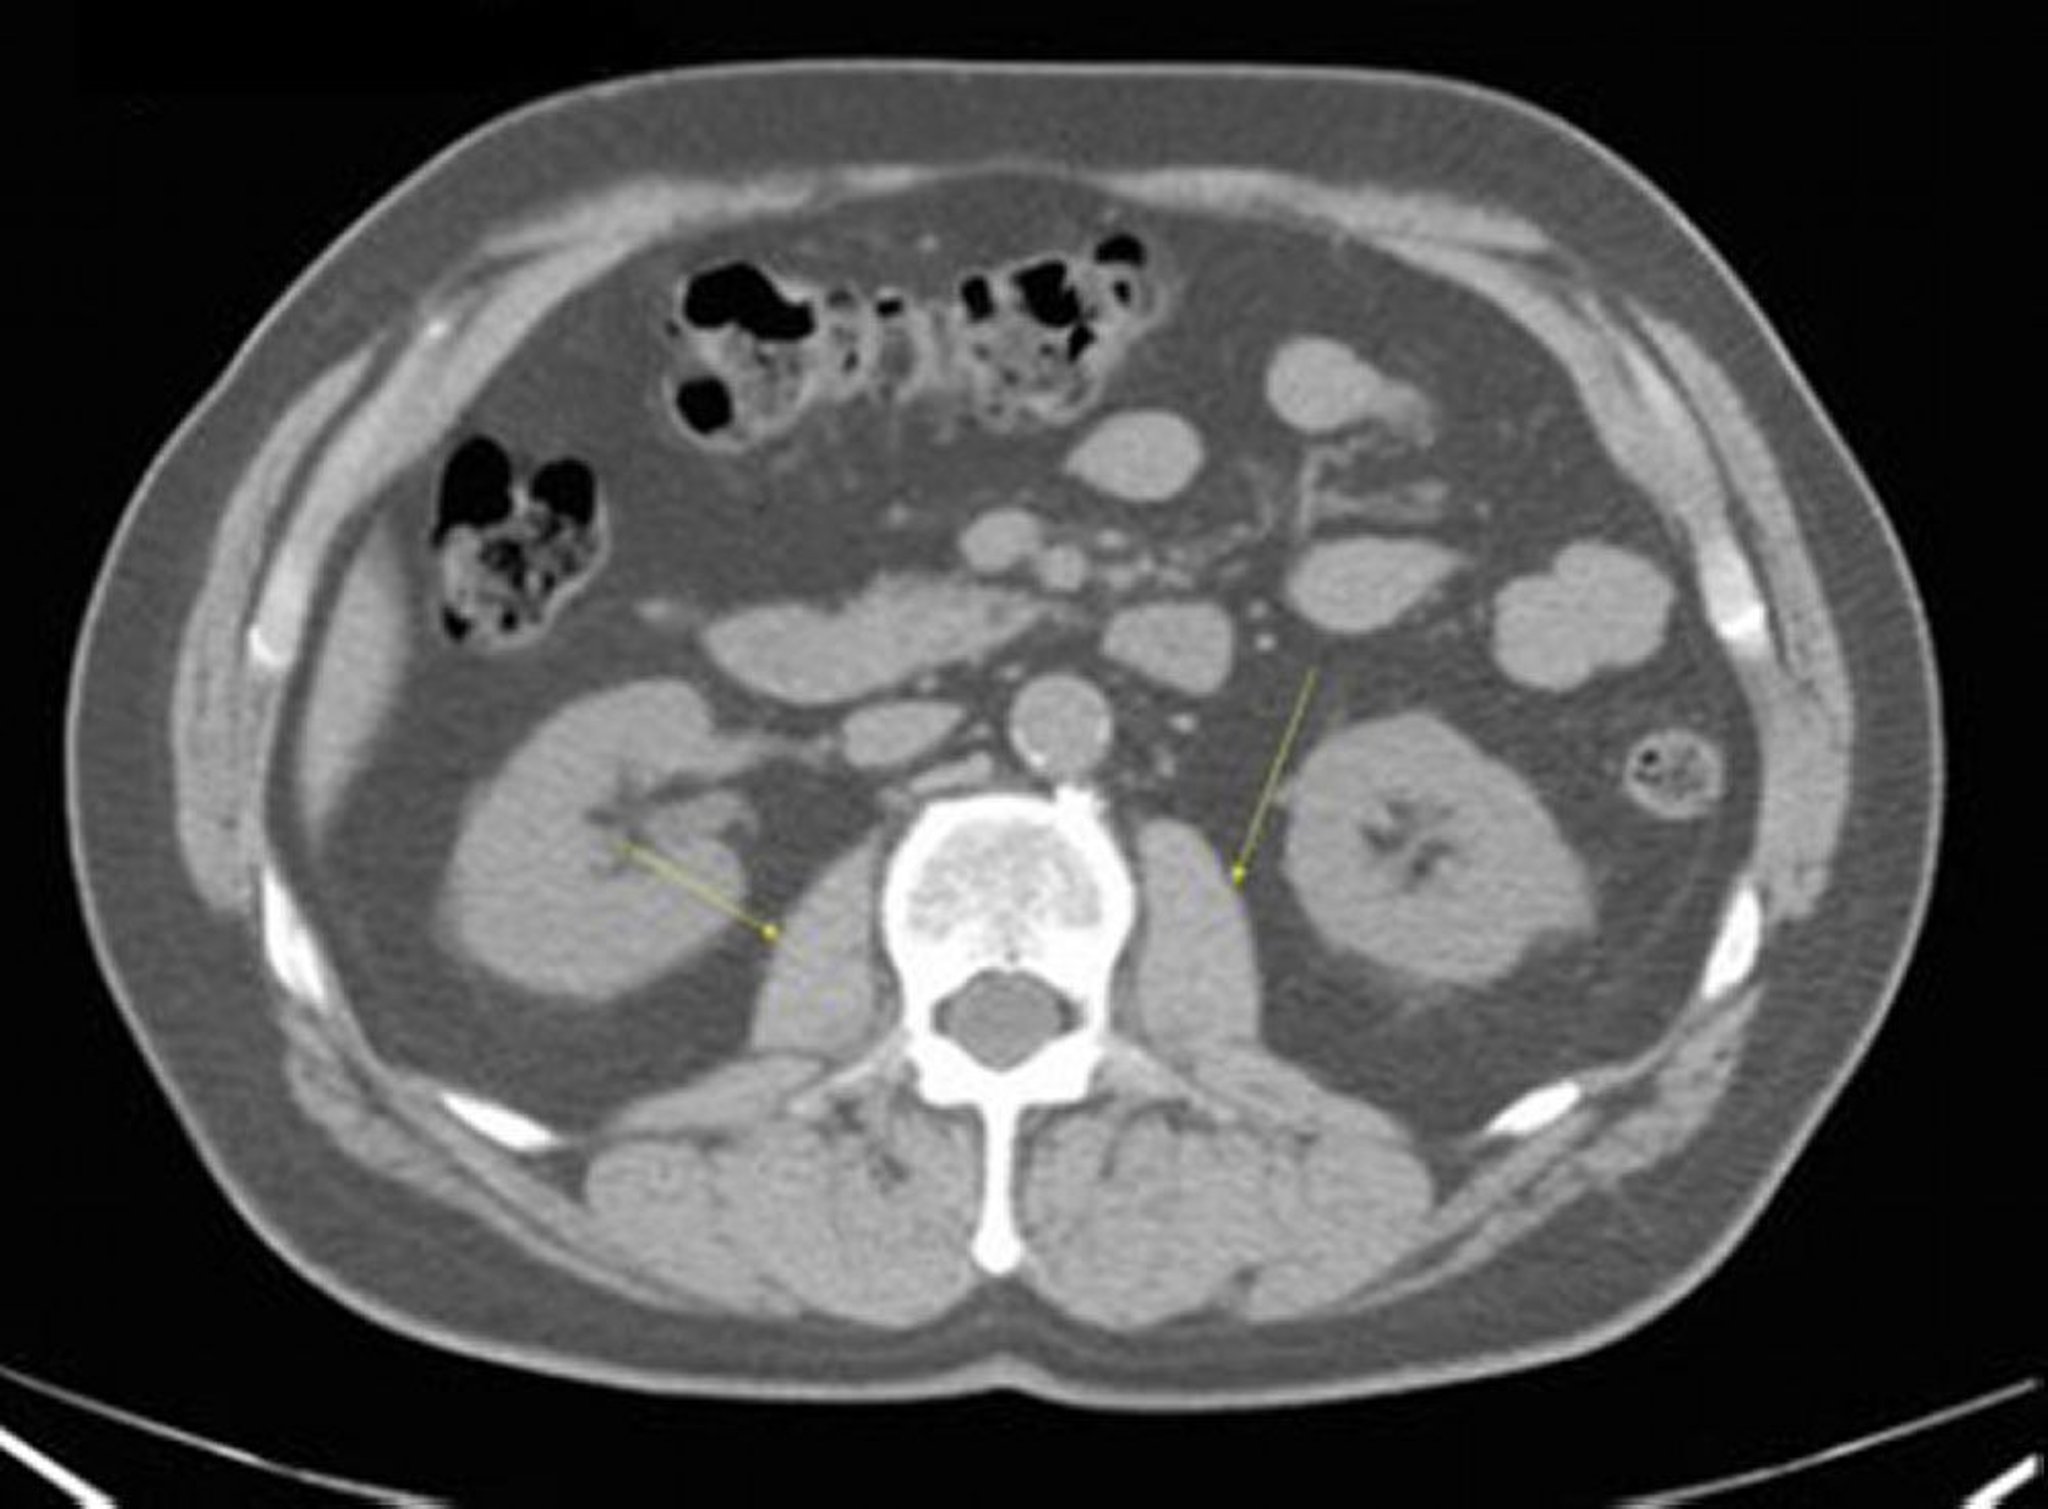

CT-Scan von Abdomen und Becken mit normaler Anatomie ohne Kontrastmittel (Folie 16)

Diese Abbildung zeigt die Psoas-Muskeln (Pfeile).